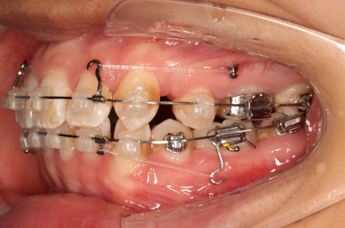

2017.10.07

2017.10.07  继续关间隙,下颌使用水平关间隙

下颌磨牙通过powerarm直立效果明显,下颌整平效果明显

2017.12.15  继续关间隙

2018.03.01上TPA加17、27颚侧牵引钩,压低17、27颚尖下颌43、32重粘,下颌0.016*25niti

2018.04.20  间隙基本关闭,上颌重新整平,精调

2018.5.25  (19个月)拆TPA,16、26粘tube 上颌0.14*25cu-niti  下颌0.018*25niti2018.7.23  上颌 0.017*25TMA,下颌0.017*25ss43压低曲,双侧后牙垂直牵引